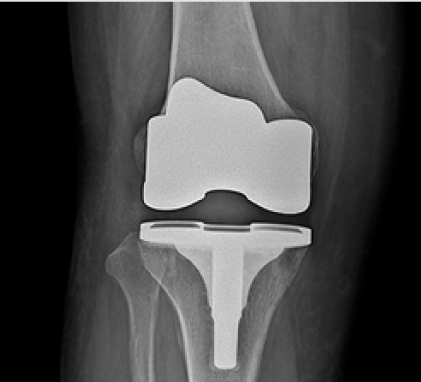

인공관절치환술이란?

연골이 손상되거나 퇴행성 변화로 인해 관절이 닳아 기능이 저하되었을 때,

손상된 부분을 제거하고 인공관절로 대체하는 수술입니다.

연골 손상이 지속되면 휴식 중에도 통증이 발생할 수 있으며, 약물치료, 주사치료, 물리치료 등의 보존적 치료에도 호전되지 않는 경우

인공관절치환술이 필요할 수 있습니다. 이 수술은 말기 관절염 환자나 무혈성 괴사 환자에게 적용됩니다.

무릎인공관절